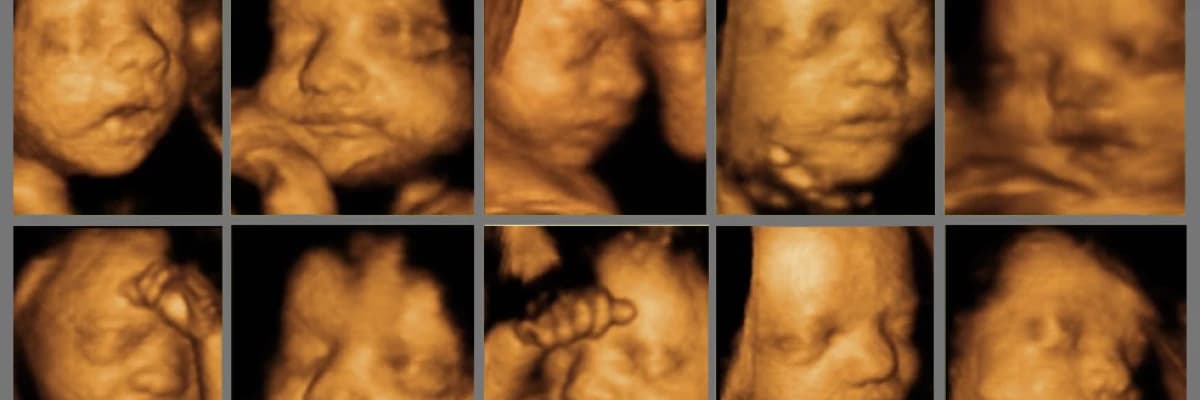

Ayrıntılı ultrason (ikinci düzey ultrason – detaylı ultrasonografi) uygulaması esnasında doktor için esas olan 3 boyutlu (3d) veya 4 boyutlu (4d) ultrason kesitleri değil, iki boyutlu ultrasonografi yani iki boyutlu ultrason kesitleridir. Uygulama esnasında uzunlamasına (1. boyut) ve enlemesine (2. boyut) kesitler alınarak bebeğin iç organları hakkında fikir sahibi olunur. Hekim gerçek zamanlı (real time) olarak ihtiyaç duyduğu ultrason kesitlerini alarak bebeği inceler.

Bebeğin yüz, vücut, el ve ayaklarının hamile anne ve baba tarafından belirgin olarak algılanmasını sağlayan üç boyutlu (3d) ve dört boyutlu ultrason (4d) görüntülerinin, aslında tıbbi olarak anatomik taramada pek de yeri yoktur. Anne ve baba, 3 boyutlu (3d) ve 4 boyutlu ultrason (4d) görüntülerinde bebeklerini daha iyi algılayıp gördükleri için, yanlış olarak hekimin de bu kesitlerde bebek hakkında daha fazla bilgi sahibi olacağını zannederler. Oysaki doktorlar bebek hakkındaki tıbbi bilgileri 2 boyutlu ultrason kesitlerini değerlendirerek edinirler. Üç boyutlu (3d) ve 4 boyutlu ultrason (4d) uygulamaları tıbbi olarak sadece bazı özel durumlarda, bebeğin bir organının değişik kesitlerinin aynı anda değerlendirilmesi gerektiğinde kullanılır.